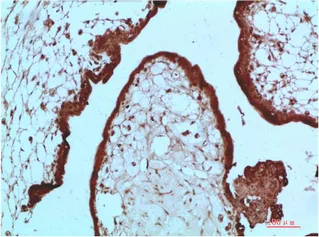

HER2(11H9)Mouse Monoclonal Antibody

Cat: AMM11986

Size1:50μL Price1:$118

Size2:100μL Price2:$220

Size3:200μL Price3:$380

Application:WB,IF-P,IF-F,ICC/IF,IHC-P

Reactivity:Human,Mouse,Rat

Conjugate:Unconjugated

Optional conjugates: Biotin, FITC (free of charge). See other 26 conjugates.

Gene Name:ERBB2